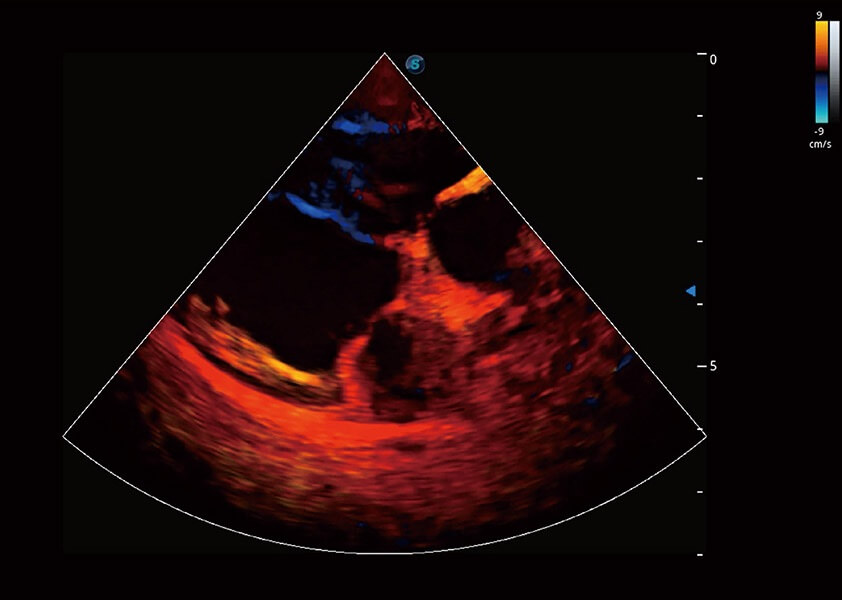

优异的基础图像

(犬)四腔心血流

• TDI 组织多普勒成像

实时用颜色表示心肌组织运动,观察和定量组织的运动情况,对快速检测与评估心肌的灌注和活性、电传导及心肌收缩和舒张功能等均能提供重要的诊断信息。